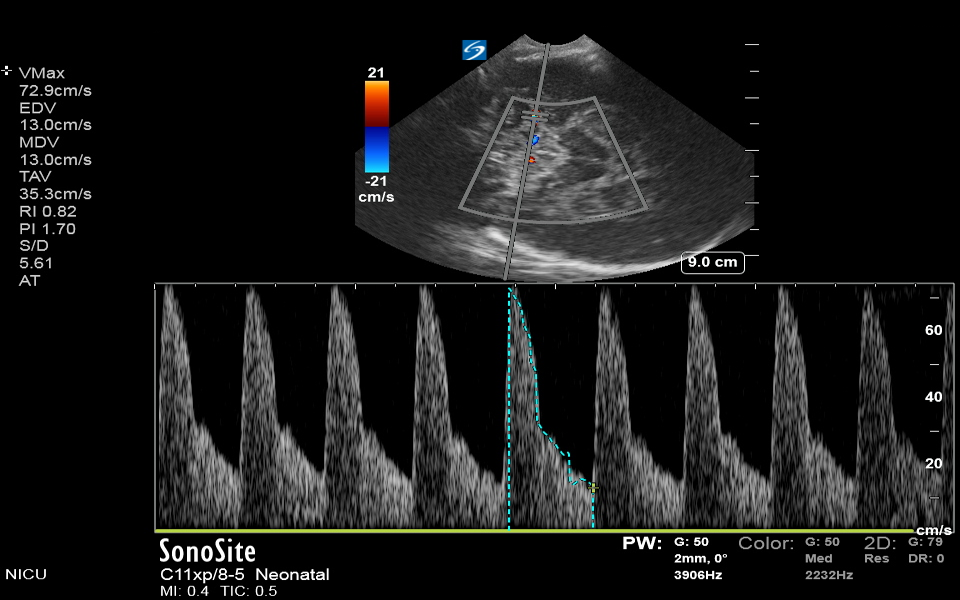

Neonatology Middle Cerebral Artery Doppler Normal Image